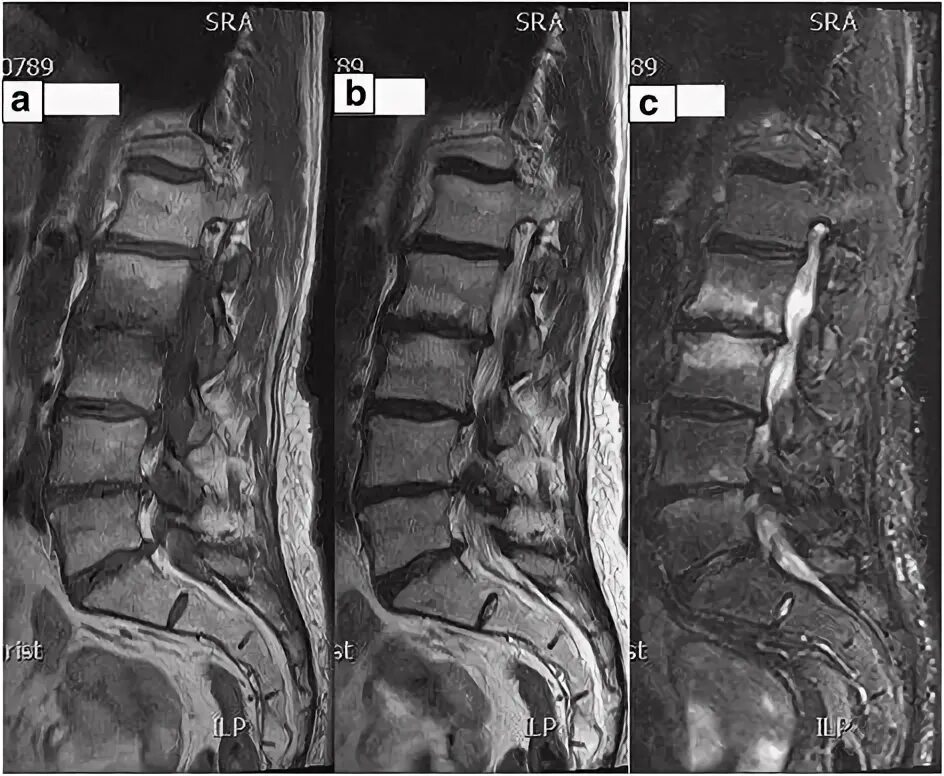

Изменения modic 2